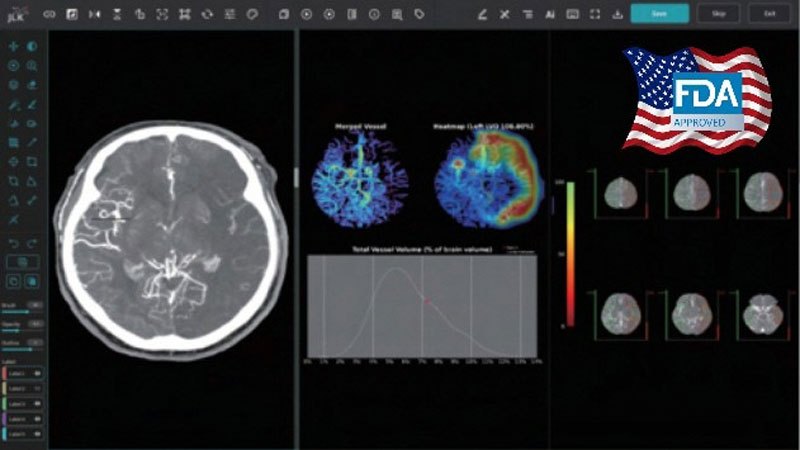

310170_215835_4659.jpg

제이엘케이 대혈관폐색 검출 설루션 JLK-LVO [제이엘케이 제공=연합뉴스]